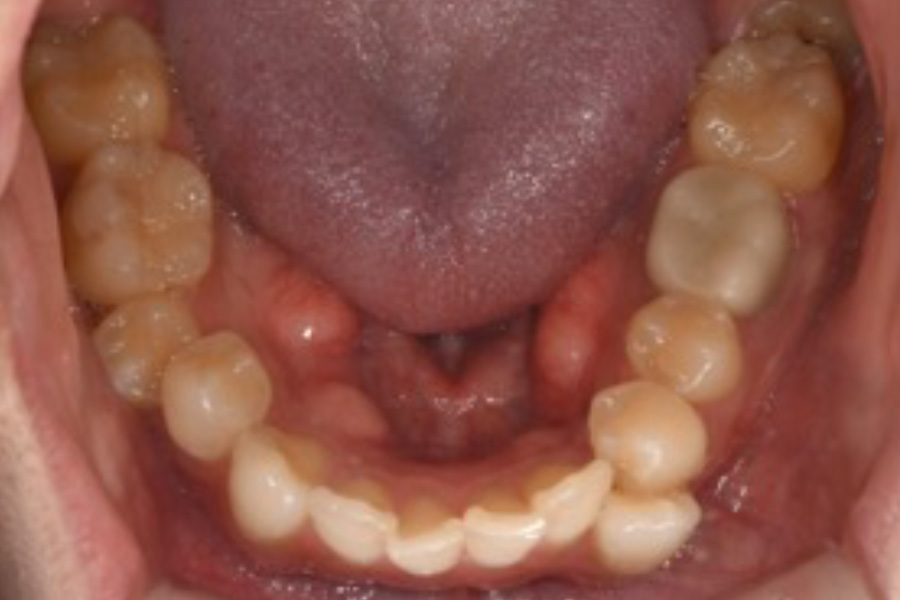

治療前

治療後

主訴 八重歯を含めた全体的なガタつき

治療内容 目立ちにくいマウスピース矯正(非抜歯矯正)

歯と歯の間に隙間をつくることにより、歯列弓を広げながら治療を行いました。